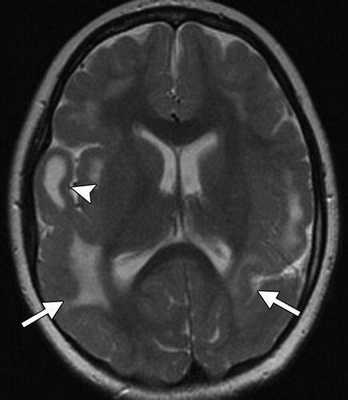

Кроме выраженной вентрикуломегалии, определяются множественные кальцификаты (стрелки), расположенные перивентрикулярно.

Рисунок 2 | Некрупные кальцификаты (стрелки) базальных ядер с двух сторон у ребенка с ЦВИ-энцефалитом.

Двустороннее расширение боковых желудочков, гиперинтенсивный очаг белого вещества правой лобной области (головка стрелки) и диффузная пахигирия — извилины мозга в указанной области выглядят широкими и уплощенными.

Видно множественные гиперинтенсивные субкортикально расположенные очаги воспаления паренхимы мозга (стрелки), а также участок кистозной трансформации в правой височной области (головка стрелки).